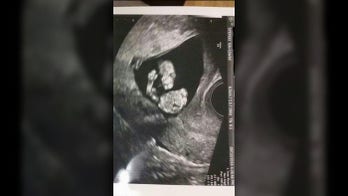

Georgia baby salutes Marine dad in utero Some parents see their own features in their babies when looking at a prenatal ultrasound, but one Georgia mom saw her future child’s patriotism.